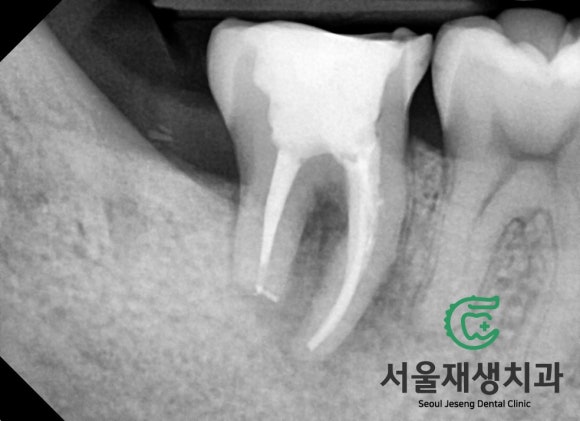

원활한 치료를 위해 일단 사랑니를 빼야겠습니다.

그리고 신경치료를 시작합니다.

서울재생치과의 트레이드마크인

마라톤 신경치료가 시작됩니다.